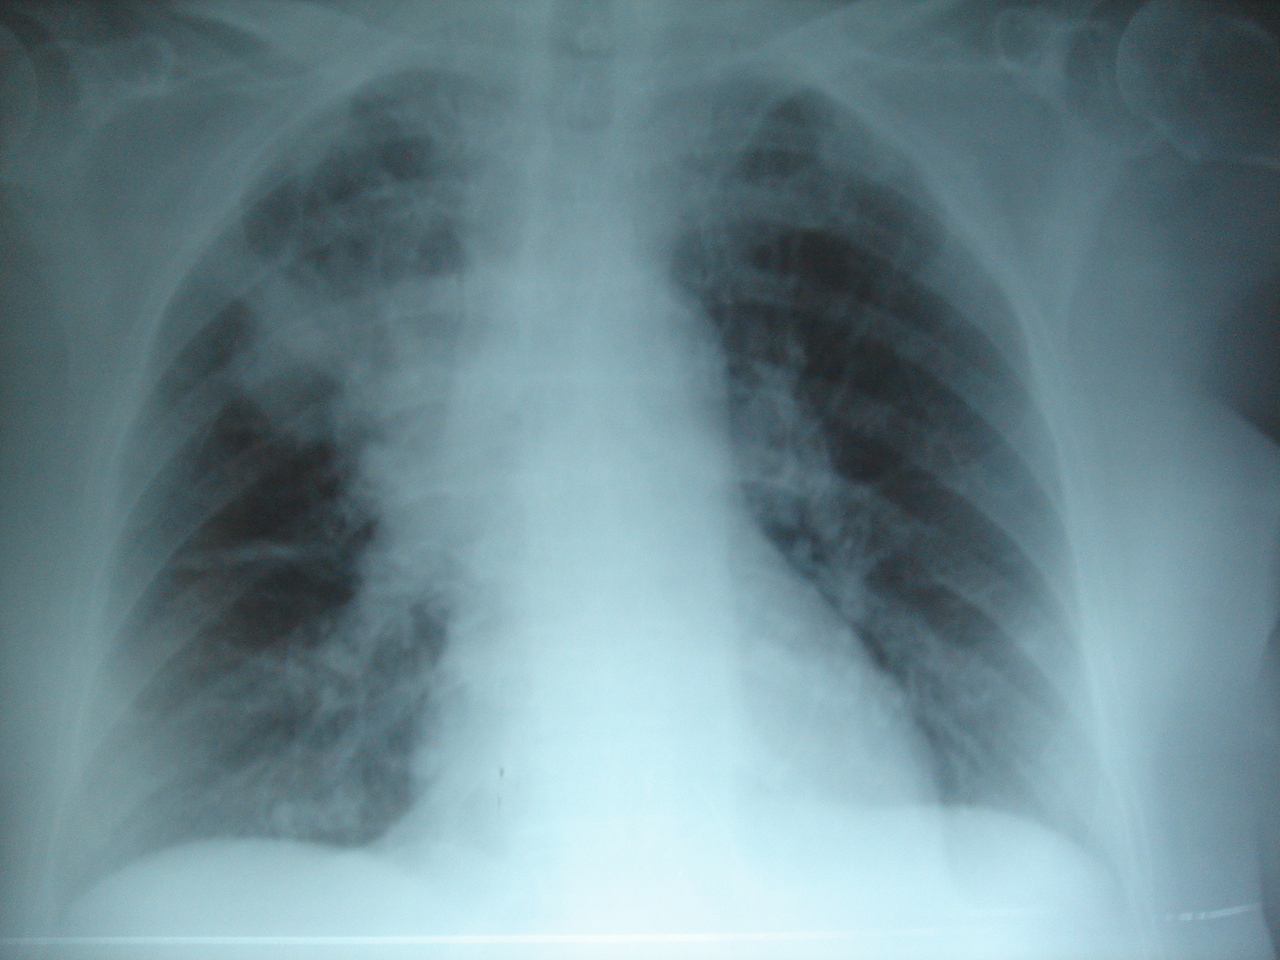

Фото: No machine-readable source provided. Own work assumed (based on copyright claims), No machine-readable author provided. Joseaperez assumed (based on copyright claims), Creative Commons Attribution-Share Alike 3.0 Unported license.